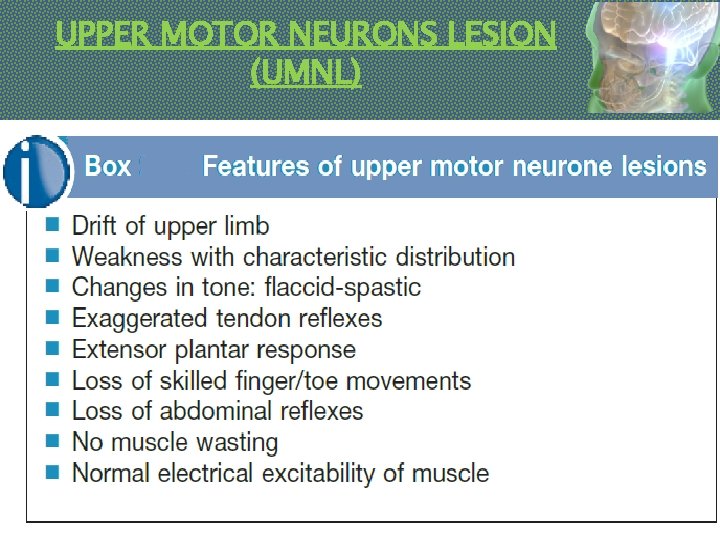

UPPER MOTOR NEURONS LESION (UMNL).

Pyramidal Drift Of An Upper Limb Normally, the outstretched upper limbs are held symmetrically, when the eyes are closed. With a pyramidal lesion, when both upper limbs are held outstretched, palms uppermost, the affected limb drifts downwards and medially. The forearm tends to pronate and the fingers flex slightly. This sign is often first to emerge, sometimes before weakness and/or reflex changes become apparent.

Weakness And Loss Of Skilled Movement Ø A unilateral pyramidal lesion above the decussation in the medulla causes weakness of the opposite limbs. Ø When acute and complete, this weakness will be immediate and total, a hemiplegia, e. g. following an internal capsule infarct. Ø With slowly progressive lesions (e. g. a hemisphere glioma) a characteristic pattern of weakness emerges – a hemiparesis. Ø There is also loss of skilled movement – fine finger and toe control diminishes.

Changes In Tone And Tendon Reflexes Ø An acute lesion of one pyramidal tract (e. g. internal capsule stroke) causes initially FLACCID paralysis with loss of tendon reflexes. Ø Increase in tone follows, usually within several days due to loss of inhibitory effects of the corticospinal pathways and an increase in spinal reflex activity. Ø SPASTICITY is characterized by sudden changing resistance to passive movement – the clasp-knife effect. Ø Relevant TENDON REFLEXES become exaggerated; Ø CLONUS may emerge.

Changes In Superficial Reflexes Abdominal (and cremasteric) reflexes are abolished on the side affected. The Babinski sign.